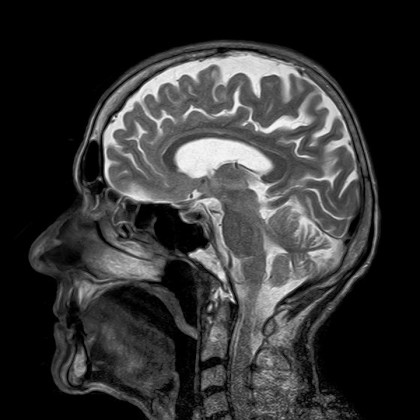

Cercetătorii din cadrul Centrului de Imagistică Biomedicală Athinoula A. Martinos de la Spitalul General Massachusetts au dezvoltat o tehnică nouă bazată pe inteligență artificială È™i algoritmi de învățare mecanică (machine learning), permiÈ›ând achiziÈ›ia de imagini de calitate superioară mai rapid È™i mai eficient.

Tehnica este numită AUTOMAP (automated transform by manifold approximation) È™i a fost prezentată într-un articol publicat în jurnalul Nature.

Sistemul AUTOMAP permite o vizualizare mai detaliată, mai puțin mecanică și inspirată de creierul uman, ce se poate adapta la date concrete din lumea reală. Permite strategii computaționale mai eficiente pentru a obține imagini clare, precise pentru o varietate de scenarii.

AUTOMAP ar putea oferi numeroase beneficii în practica clinică, de la producerea de imagini de înaltă calitate în timp mai scurt pentru RMN sau reducerea dozelor de radiaÈ›ii în radiografii, scanări CT sau PET. Datorită vitezei de procesare, tehnica ar putea duce la procese decizionale chiar È™i în timpul scanării pacientului. Sistemul ar putea fi utilizat în alte aplicaÈ›ii de inteligență artificială ca cele de diagnostic în timp real.